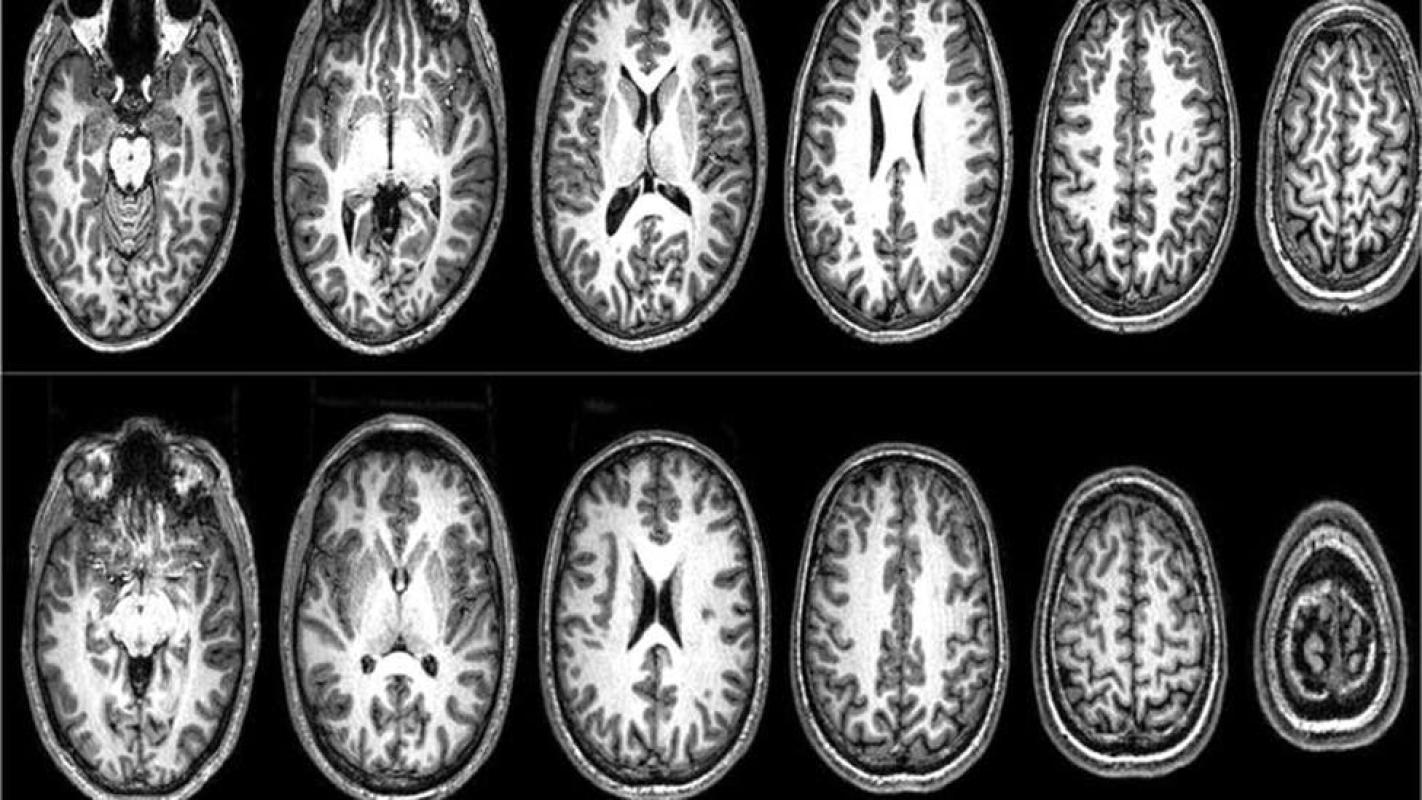

Para los escáneres cerebrales utilizamos una técnica llamada imagen por resonancia magnética funcional (IRMf), que registra e identifica las áreas del cerebro que están activas durante tareas específicas.

Desde un punto de vista neurológico, los valores sagrados activaron el giro frontal inferior izquierdo, una zona asociada con el procesamiento de normas, y ya relacionada anteriormente con los valores sagrados en estudiantes universitarios estadounidenses.

Sin embargo, en el caso de los que habían resultado excluidos aumentó la disposición a luchar y morir por valores no sagrados, y el giro frontal inferior izquierdo se activó incluso durante el procesamiento de los valores no sagrados.

Estos participantes mostraron un patrón diferente de actividad neuronal con respecto a los marroquíes del primer estudio, que tenían los mismos patrones que los estudiantes universitarios de Estados Unidos.

A medida que los hombres pakistaníes altamente radicalizados iban evaluando sus valores sagrados, se produjo una desactivación en una red que incluye la corteza dorsolateral prefrontal (DL-PFC), una zona del cerebro que se asocia con el razonamiento deliberativo y la integración de cálculos de coste-beneficio.

Cuando calificaron como alta la disposición para luchar y morir por sus valores, descubrimos un aumento de la activación en la corteza prefrontal ventromedial (VM-PFC), una zona del cerebro que se asocia con la valoración subjetiva (¿cuánto valor tiene esto para mí?).

En el día a día, estas dos zonas del cerebro trabajan de forma conjunta en la toma de decisiones.

En un análisis de seguimiento se descubrió que esas dos regiones del cerebro estaban muy conectadas cuando los participantes calificaban como baja su disposición para luchar y morir; es decir, el valor subjetivo estaba limitado por los mecanismos de control de costes y beneficios.

Pero cuando calificaban como alta la disposición para luchar y morir, descubrimos que esas dos regiones estaban más desconectadas.

Esto sugiere que, cuando alguien está listo para matar o morir en defensa de una idea, ya no utiliza los mecanismos de control que suelen participar en el razonamiento deliberativo.

Básicamente, desconectan esta parte del cerebro. Sin embargo, su disposición para luchar y morir disminuye a medida que las regiones de valoración deliberativa y subjetiva se vuelven a conectar. Entonces, ¿qué mecanismos llevan a las personas a reducir su disposición para luchar y morir por una causa?

Este cambio tuvo su correlación con una mayor activación de la corteza dorsolateral prefrontal en el cerebro. Sus vías deliberativas se estaban reabriendo.